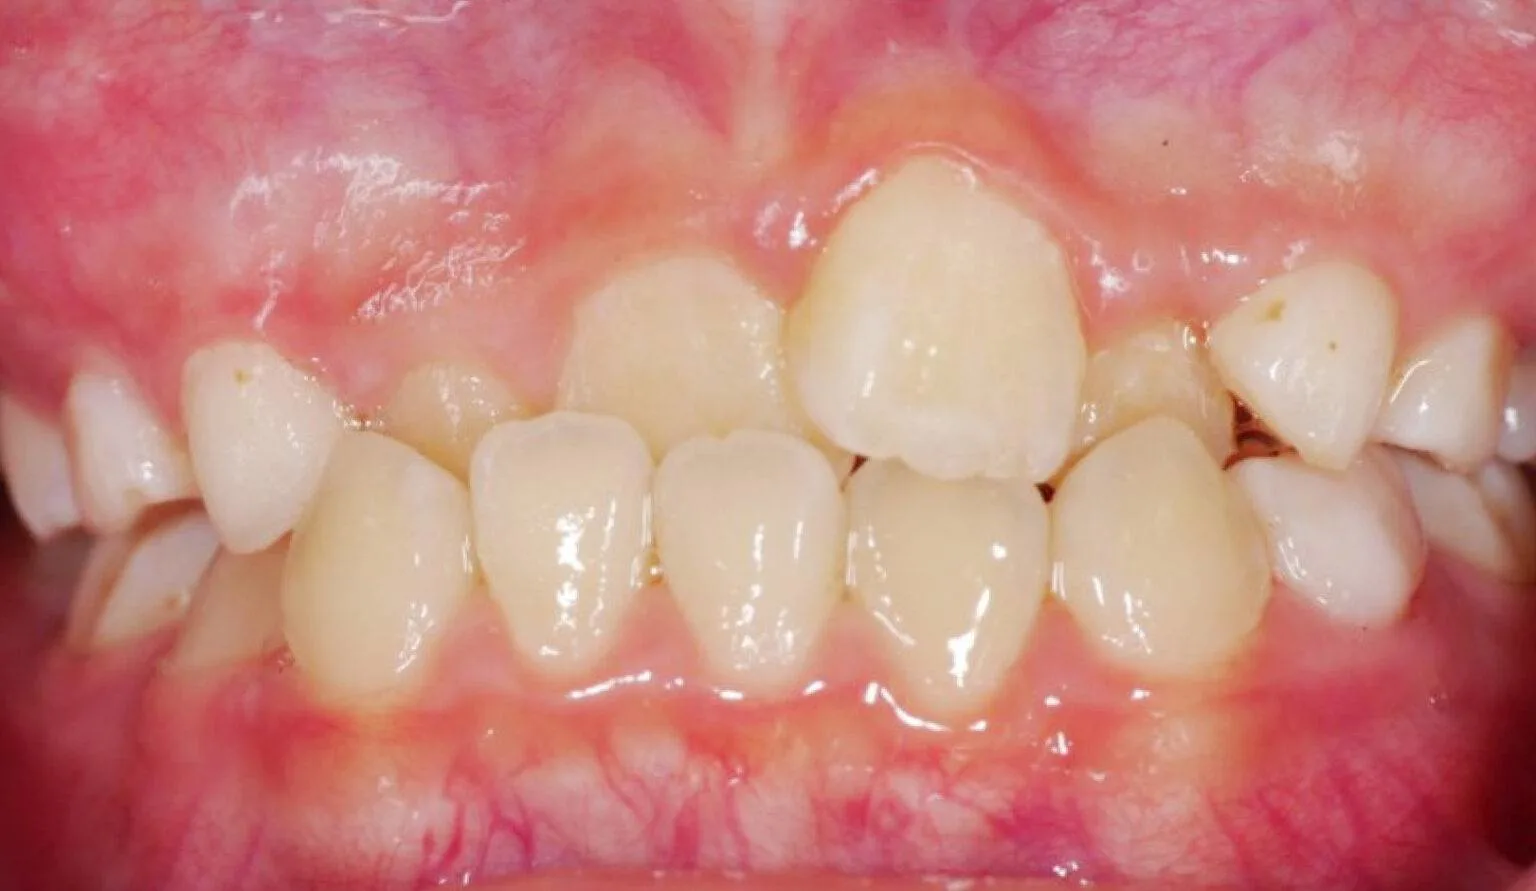

6 Types of common tooth misalignment that Invisalign® can resolve

Overcrowding is a common teeth misalignment which occurs due to lack of space in the oral cavity for the teeth. This makes the teeth grow to be crooked and/or overlap with each other. This creates an overcrowded atmosphere in the mouth and can lead to poor oral hygiene due to the inability to clean the teeth efficiently.